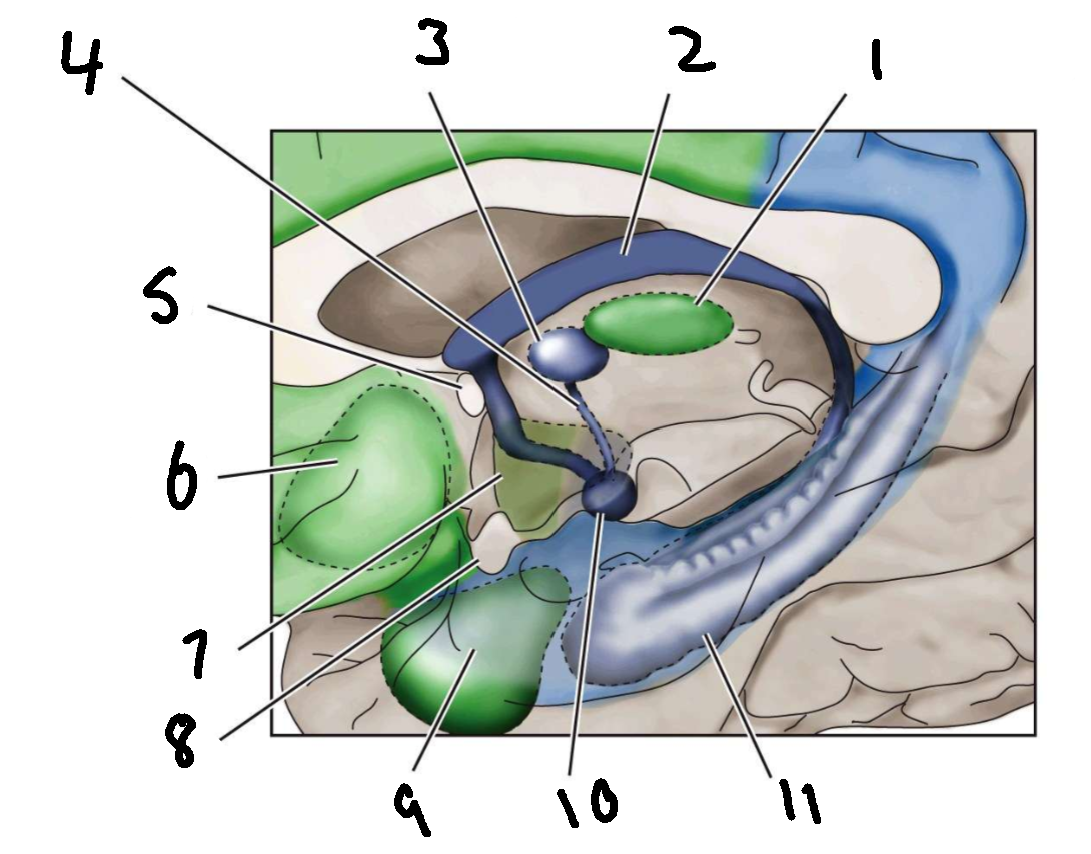

What is 1?

mediodorsal nucleus of the thalamus

What is 2?

fornix

What is 3?

anterior nucleus of the thalamus

What is 4?

mammillothalamic tract

What is 5?

anterior commissure

What is 6?

ventral basal ganglia

What is 7?

hypothalamus

What is 8?

optic chiasm

What is 9?

amygdala

What is 10?

mammillary body

What is 11?

hippocampus